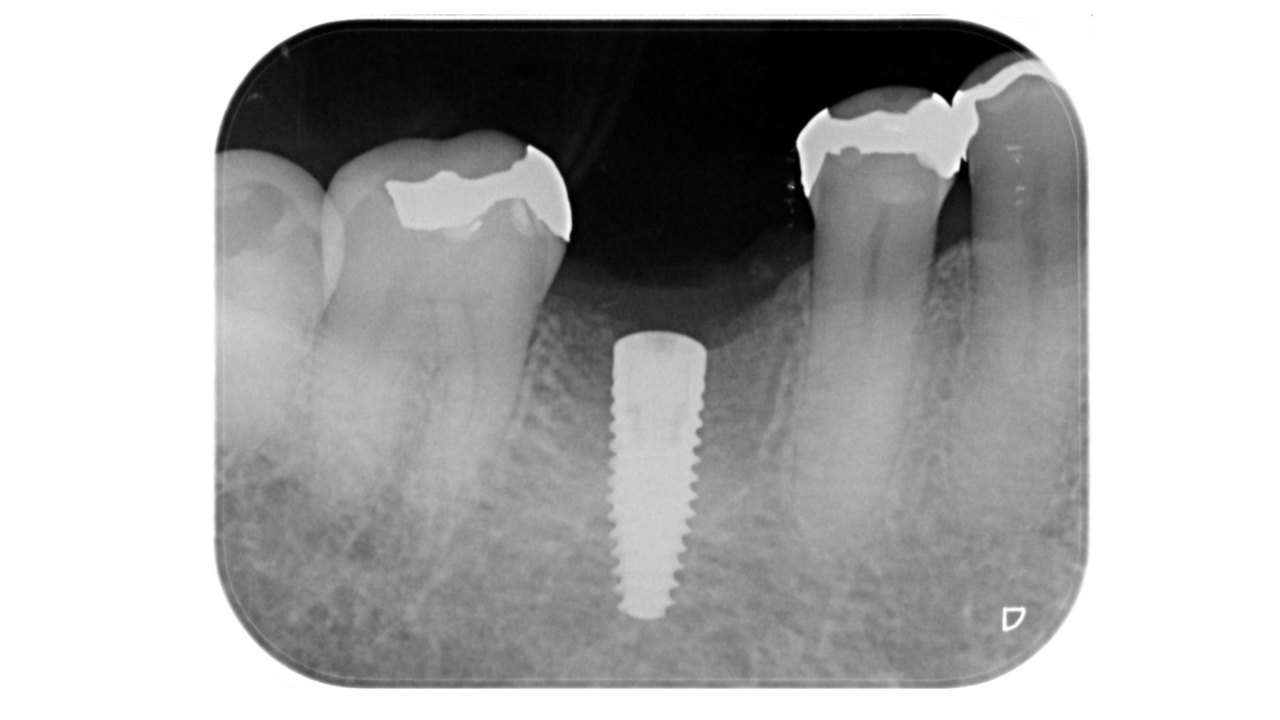

Y・F様 女性 70代

Before

After

以前から左下奥歯がなく硬いものが噛めず、かみ合わせが不安定なため、欠損部にインプラント治療を希望され、治療を開始。治療後、奥歯でしっかり噛めるようになり、食事も美味しく食べれるようになったと満足されていました。

治療期間・回数:7か月、10回

治療の価格:インプラント治療  550,000円 (上部構造含む)

治療のリスクや副作用:手術後に、痛みや腫れ、出血、合併症などを引き起こす可能性があります。噛む感覚がご自身の歯と異なる場合があります。見た目がご自身の歯と異なる場合があります。手術後にメインテナンスを継続しないと、インプラントが脱落するリスクがあります。